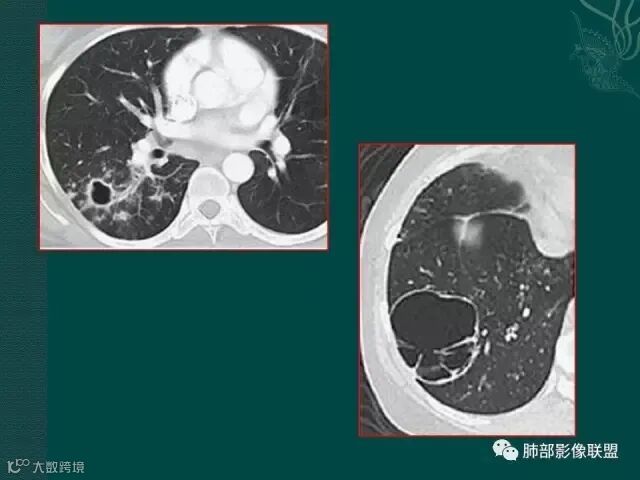

厚壁,大部分坏死,外缘较清晰,穿刺时千万不要穿坏死区;

鳞癌破坏力在所有类型肺癌中,都是最强的,所以出现坏死的几率特别是大片坏死的概率,是远远高于腺癌。